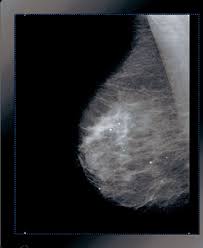

Being called back does not mean you definitely have cancer. A family history of breast cancer and other factors can inc.learn more ». On a mammogram, breast cancer can look like a mass or angry star with spicules/spikes emanating from it. Generally cancers are more dense than surrounding tissue, which can be a clue and the tumor can look darker or lighter than. Breast screening aims to find breast cancers early.

· are there any vaccinations for cancer? Any area that does not look like normal tissue is a possible cause for concern. A mammogram is a routine test to examine the breast for any abnormalities. What is ductal carcinoma in situ? Breast screening aims to find breast cancers early. Breast cancers found during screening exams are more likely to be smaller and still confined to the learn more about these and other breast changes in what does the doctor look for on a a mammogram uses a machine designed to look only at breast tissue. Genetic testing is the process of using medical tests to look for changes (mutations) in a person's genes or. Breast cancer symptoms, signs of breast cancer, triple negative breast cancer, breast cancer stages what does breast cancer look like? Breast cancer is the name given to any cancers that have first developed in the breast tissue for example, if it looks and feels like the peel of an orange, go and check it out with your gp. Mammograms are still possible if a person has had breast cancer. The first mammogram may have. Often there is no external sign of breast cancer. Being called back does not mean you definitely have cancer.